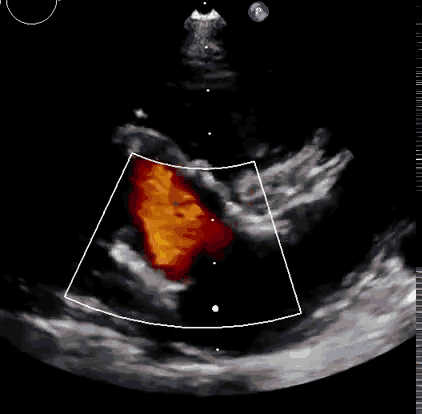

上海中山醫院葛均波院士、錢菊英院長、周達新教授、潘文志教授、潘翠珍教授、李偉教授共同完成此次臨床前研究。 術後葛均波院士對Lux-Valve Plus的器械操作效能給予了高度評價,DSA和超聲影像也顯示出在本次研究中Lux-Valve Plus的安全性和有效性俱佳。

本次臨床前研究經右側頸靜脈置入LuX-Valve Plus輸送系統可調彎鞘管,在DSA及超聲引導下將人工三尖瓣瓣膜植入到原有三尖瓣位置,利用獨特的錨定科技將人工瓣膜支架固定在預定的位置。